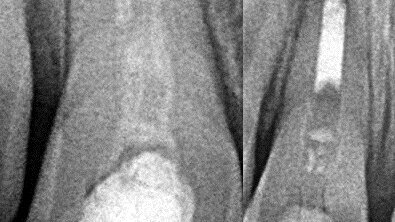

Dva dana ranije, u saobraćajnoj nezgodi, malu Marlenu udario je automobil. Na desnom gornjem centralnom sekutiću bila je prisutna fraktura gleđi i ...